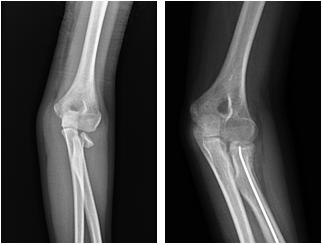

Fratture e distacchi del massiccio condiloideo dell'omero distale - Frattura sovracondiloidea

Nelle fratture composte o modicamente scomposte il trattamento è sempre conservativo con gomitiera gessata e adeguato monitoraggio radiografico.

Nel caso di frattura trasversa, a 2 frammenti, con scarso spostamento dei monconi e nei pazienti più piccoli è indicato tentativo di riduzione incruenta della frattura, previo congruo periodo di trazione su balcanica. Ottenuta la riduzione, la frattura deve essere immobilizzata in apparecchio gessato toraco-brachiale. Nelle fratture scomposte con marcata componente rotatoria è possibile procedere dopo riduzione incruenta alla stabilizzazione con fili di Kirscher percutanei con configurazione incrociata o parallela a seconda del tipo e della sede della frattura.

Nelle fratture con edema/tumefazione marcata del gomito (specie se vi è stata latenza temporale fra il momento del trauma e la presentazione in Pronto Soccorso), nel caso sia presente un deficit neurologico, in caso di insuccesso della manovra riduttiva (per interposizione di tessuto muscolare o periosteo o grave comminuzione della frattura) è indicata la riduzione cruenta con approccio laterale, postero-laterale o posteriore e sintesi mediante fili di Kirschner. In caso di potenziale lesione nervosa del nervo mediano o radiale o dei vasi omerali è necessario utilizzare un approccio antero-laterale con esplorazione chirurgica vascolo-nervosa.

Per l'immobilizzazione post-operatoria è sufficiente una gomitera gessata con bendaggio reggibraccio. Successivamente in base all'evoluzione radiografica (callo di frattura) e alla stabilità dell'eventuale osteo-sintesi si deciderà se iniziare la mobilizzazione del gomito o proseguire con tutela (valva rimovibile o nuovo apparecchio gessato).

Le complicanze più comuni in questo tipo di fratture sono la deformità in varo/valgo da viziosa consolidazione o lesione della cartilagine di accrescimento, l'intollerenza o mobilizzazione di eventuali mezzi di sintesi (possibile necessità di rimozione precoce). Più rare sono la rigidità articolare (in particolare in flessione) e la formazione di ossificazioni eterotopiche. In genere si assiste al completo recupero di eventuali deficit neurologici a distanza di 3-6 mesi. Torna su